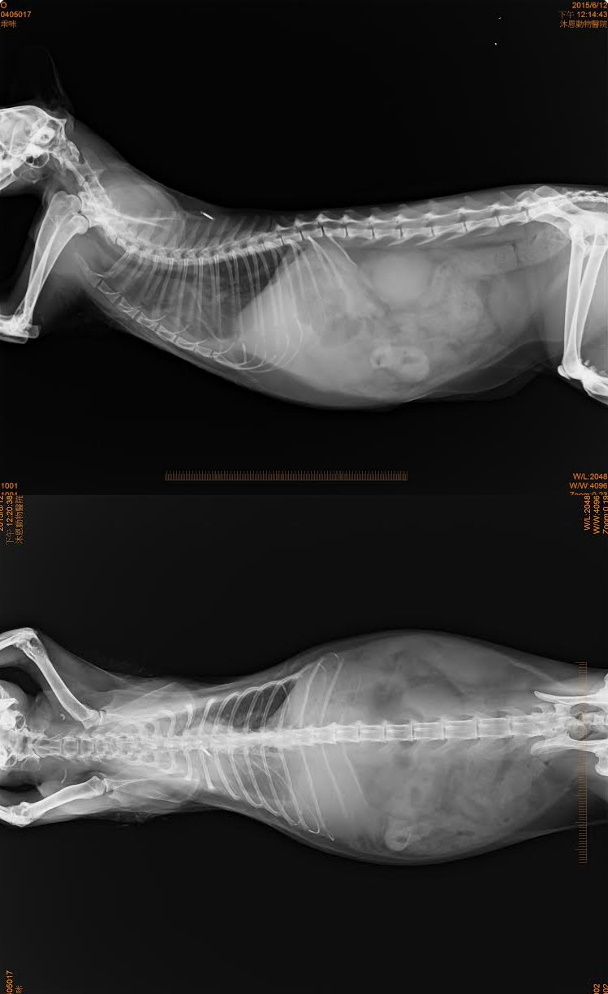

醫生觸診懷疑腹部有積水,照了超音波後確定有腹水,並抽取一管送驗、並做了血檢,已先拿幾日口服抗生素投藥,待化驗結果出爐才能做進一步的治療,這部分醫療費用由李姐支付,5/2轉院至協會配合動物醫院進行更詳細的檢查,血檢白血球3萬8,有感染的狀況,超音波檢查腹腔有腹水,檢驗膽汁酸排除肝門脈分流的問題,看診完李姐將貓咪帶回照顧,一方面可以多陪陪貓,一方面可以節省醫療費用,兩天後回診胸腹水產生速度很快,貓咪呼吸變得比較急促,鎮靜抽腹水,以期能減輕不適,並將腹水送冠狀病毒檢驗及細菌培養,先取藥一周,5/8日檢驗報告灌狀病毒核酸陽性反應,李姐的內心也很糾結,病程表現並沒有很符合一般冠狀病毒發病,且不排除同時有別的問題腫瘤與肝衰竭,醫師認為是腫瘤與冠狀病毒同時發病,目前精神食慾穩定但因為胸腹水目前出來的速度算快,預計每週都需要麻醉抽胸水,這會是比較大的醫療費用,該繼續治療還是放手,看著乖咪持續服用藥物還能夠大口大口吃飼料罐頭,又捨不得一輩子在外流離失所,終於在老年得到一個家的乖咪,就這樣離開,選擇持續治療讓這老孩子可以終老,每周固定回診拿藥抽胸腹水,乖咪過了兩個月的快樂日子,6/25日乖咪出現嚴重貧血狀況,醫師懷疑可能是腫瘤破裂導致出血,建議輸血爭取時間治療,在很臨時的情況下找到幾個熱心貓有的幫忙,順利配對為乖咪輸血,很可惜最後乖咪還是沒有度過,但這兩個月可能是他一生中最能安心睡覺的時候,不用躲避野狗追咬還有人類的驅趕,有吃不完的乾乾還有罐頭,不用日曬雨淋,還有他最愛的媽媽陪在身邊,這一生足以,李姐送走了乖咪,負擔了最後一程火化費用,已經負擔很重,一隻被好好照顧的街貓能夠享壽10年,這中間一定是付出很多心力,惟有細心觀察下才知道乖咪的變化,能及時陪伴他最後一段,李姐餵養的貓都很親他,很多傷病老殘貓都帶回照顧安置,家中也是大爆滿的狀況,每天在外辛苦餵貓,兼差賺錢多買一些飼料罐頭,就是希望這些毛孩子能吃飽一點能度過寒冬,有體力躲避危險,沉重的負擔還希望各位能夠幫忙乖咪。